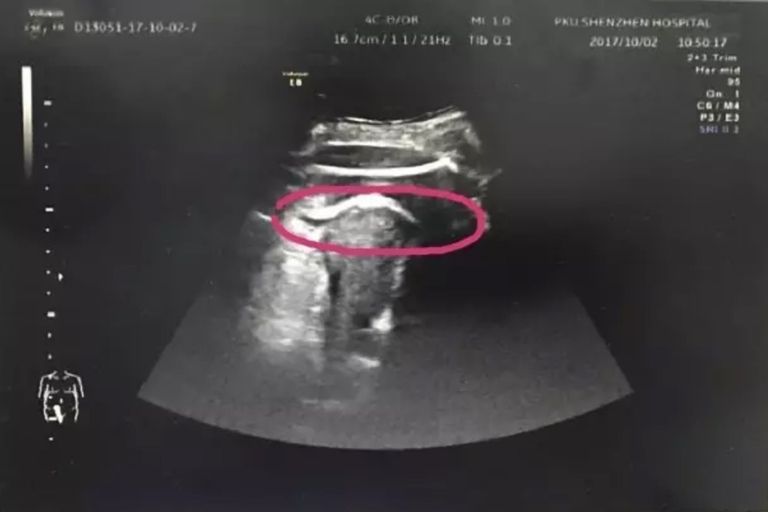

Aby potwierdzić diagnozę, zespół medyczny podjął decyzję o wykonaniu USG. Wszyscy oniemieli, gdy na USG zobaczyli, że dziecko kobiety wystawiło nogę przez dziurę w macicy. W ciągu 5 minut kobieta znalazła się na sali operacyjnej. Zdaniem lekarzy, jej nienarodzona córka tak mocno kopnęła w ścianę macicy, że ta nie wytrzymała i pękła.

(Peking University Shenzhen Hospital) Zdaniem lekarzy nienarodzona wtedy córka tak mocno kopnęła w ścianę macicy, że ta nie wytrzymała i pękła